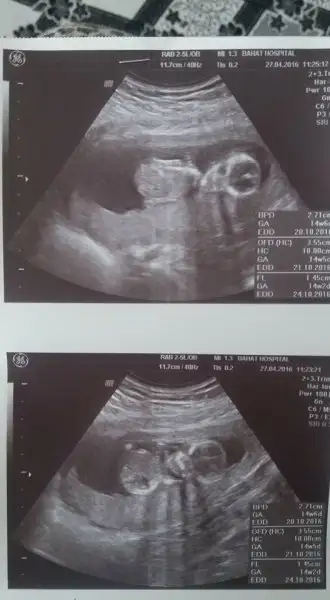

Vajinalde ve karından bakıldığında ikisinde de sağda canım,yarın resim yükleyeceğim etiketlerim seni müsaden olursa:)

Evet bekliyorum ama vajinal önce miydi tam 7 haftalik karindansa o geçerli bana at bekliyorum balim

image.webp

Canim USG nerde